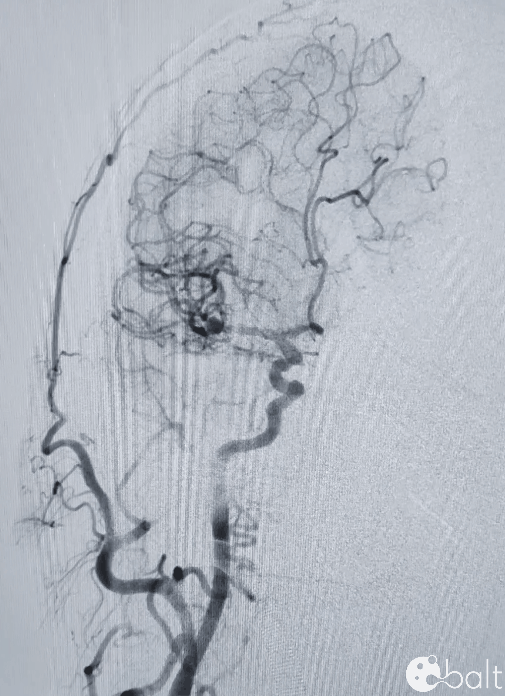

术前影像

颅脑DSA

临床诊断:右侧大脑中动脉M1分叉部宽颈动脉瘤

瘤体大小:5.04*4.56mm。